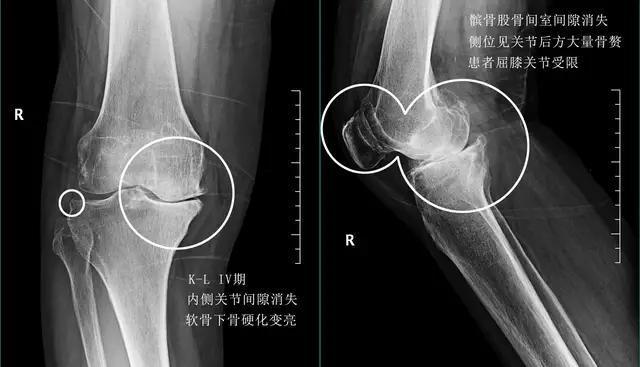

- 症状:晚期的膝关节骨关节炎会有明显的关节畸形,患者稍微行走就会有明显的关节疼痛,而且会出现明显的休息痛和夜间痛,也就是说膝盖不动的时候也会疼痛,而且患者会因为疼痛严重的影响睡眠,在夜间会疼醒。

- 诊断:后膝关节x线检查就可以明确诊断,我们可以看到关节会有大量的骨赘形成,而且有一些骨赘会影响患者的屈伸幅度,关节间隙会有进一步的狭窄,而且有些患者会因为活动减少出现严重的骨质疏松。